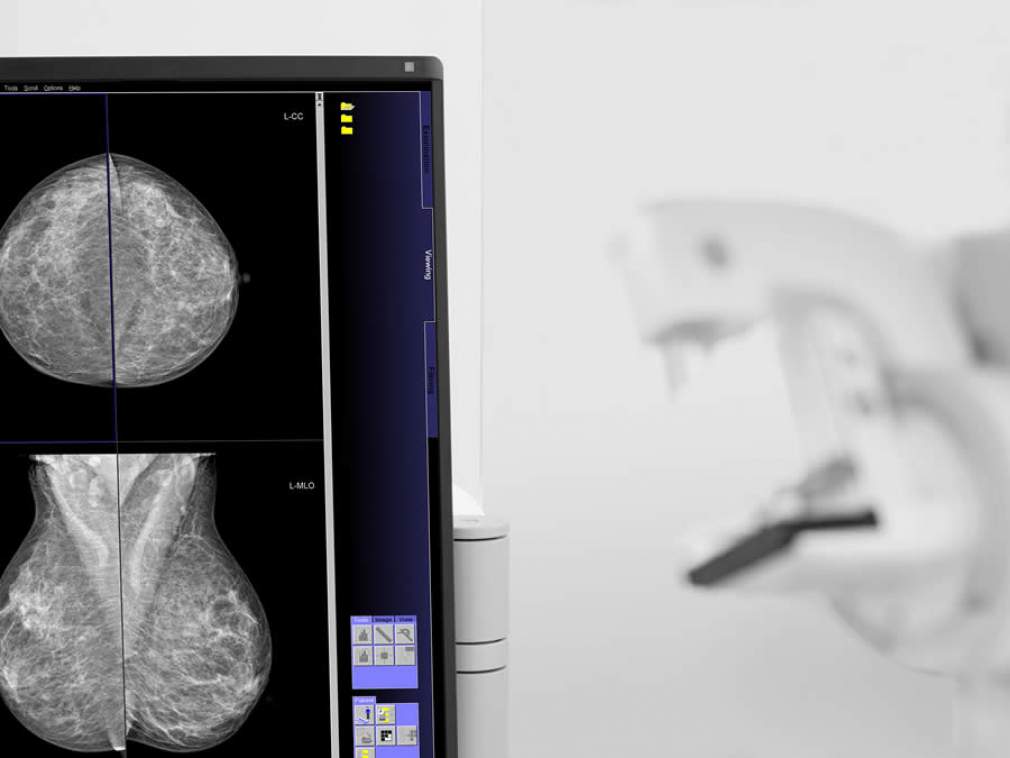

Mamografia garante detecção precoce de câncer de mama, o que eleva as chances de cura para 95%

Hospital Dona Helena implanta equipamento digital

Em Joinville (SC), o Hospital Dona Helena acaba de implantar um novo mamógrafo, totalmente digital, como parte da modernização do Centro de Diagnóstico por Imagem (CDI): o Mammomat Fusion, da marca Siemens. Os equipamentos digitais, mais avançados que os de tecnologia analógica, permitem diagnosticar o câncer ainda em pequenos focos de calcificação. Entre os benefícios, um conforto maior para as pacientes que realizam o exame – o equipamento exerce uma compressão mais adequada, que se adapta melhor à anatomia da mama. Ainda gera imagem com qualidade superior, com doses otimizadas de radiação nas diferentes espessuras e densidades do tecido mamário.